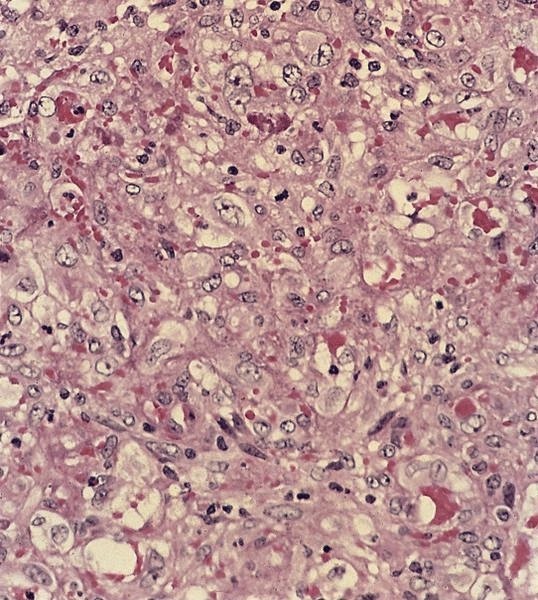

Microscopic (histologic) description

Microscopic (histologic) images

Contributed by Mark R. Wick, M.D.

Microscopic (histologic) description

- Either multiple small epithelioid granulomas or huge epithelioid granulomas with prominent Langhans giant cells and central necrosis (J Clin Pathol 1988;41:93)

Microscopic (histologic) images

Contributed by Mark R. Wick, M.D.